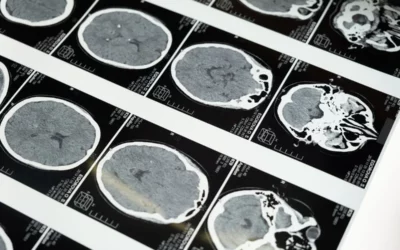

Hyperbaric Oxygen Therapy is Helpful for Neurological Disorders

Neurological disorders, ranging from mild traumatic brain injuries (mTBI) and post-traumatic stress (PTSD) to Alzheimer's disease and Parkinson's disease, have long posed significant challenges for patients and healthcare professionals alike. In the search for...